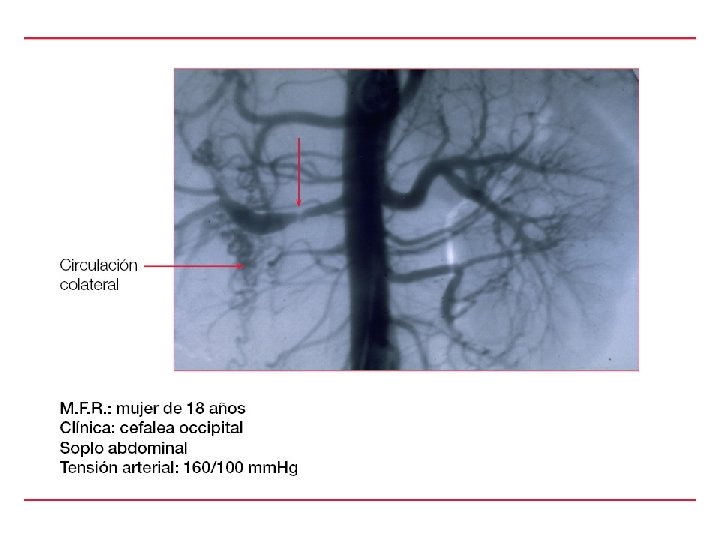

LAS ETIOLOGIAS SECUNDARIAS C- ENDOCRINAS ALDOSTERONISMO PRIMARIO SX DE CUSHING HIOERTIROIDISMO D- CARDIOVASCULAR COARTACION DE LA AORTA ETUMOR DE WILMS FEOCROMOCITOMA TUMORALES